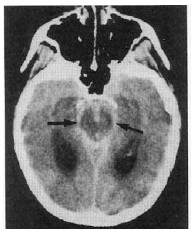

Com relação à imagem mostrada na figura acima, julgue os itens que se seguem.

Embora a hipertensão arterial (HTA) aumente o risco de repetição da hemorragia intracerebral, o tratamento da HTA é assunto controvertido na presença de hemorragia intracerebral aguda. A tendência atual é tratar-se o paciente quando a pressão sistólica ultrapassar 180 mmHg.